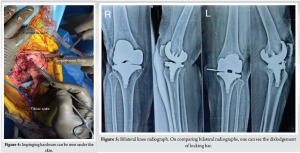

One year postoperatively patient presented with localized painless swelling over medial aspect of knee associated with palpation of hardware, which was first noticed by the patient 4 months back not associated with any trauma and has remained constant since then. On examination, the patient had mild discomfort – with maintained ROM up to 120°. There was a small, localized swelling over medial aspect of knee, which, on superficial palpation, revealed impinging hardware (Fig. 4). Radiographs (Fig. 5) demonstrated the backing out of the locking clip, which is inserted in a medio-lateral manner to keep the polyethylene insert in its place (linear locking mechanism using tongue and groove), with the polyethylene insert being in its place. Immediate post-operative radiographs and radiographs taken at follow-up were examined to confirm the correct initial position of the locking clip.

The patient was undertaken for surgery at the earliest possible time, so as to prevent complete perforation of skin and soft-tissue compromise. Medial para-patellar approach through the previous incision was undertaken. Intraoperatively, the locking clip was found to buttonhole through the medial capsule into the subcutaneous tissue (Fig. 6). The polyethylene insert was in its place (Fig. 7) on the tibial baseplate without any evidence of subluxation. The flexion and extension gaps were assessed and were found to be well balanced. The polyethylene insert was removed after subluxating Tibia and no significant wear was seen on either surface. Subluxation of tibia was facilitated by removing the posterior cruciate ligament, performing a quadriceps snip (Fig. 8) and subperiosteal release of anterior portion of superficial medial collateral ligament (Fig. 9) [3]. The CR polyethylene insert was removed and replaced with an anterior stabilizing or deep dish polyethylene insert of 10 mm (Fig. 9-11). Standard post-operative closure was performed. The post-operative course was uneventful with patient achieving full ROM at 1 week without any extension lag. Intraoperatively, samples were collected and sent for culture sensitivity which tested negative.